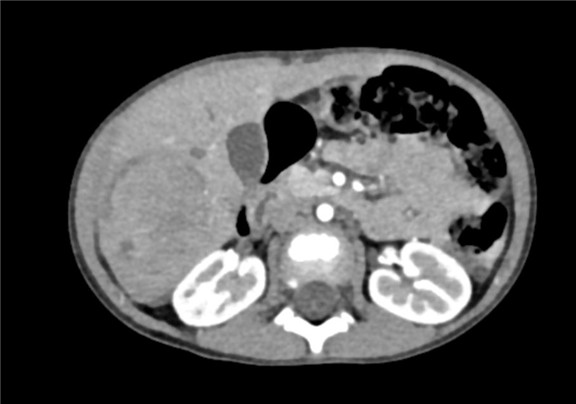

下腹部增强CT示:肝右叶较大肿块影,考虑恶性肿瘤(肝母细胞瘤)可能性大,较前减小

术前CT检查:

动脉期

静脉期